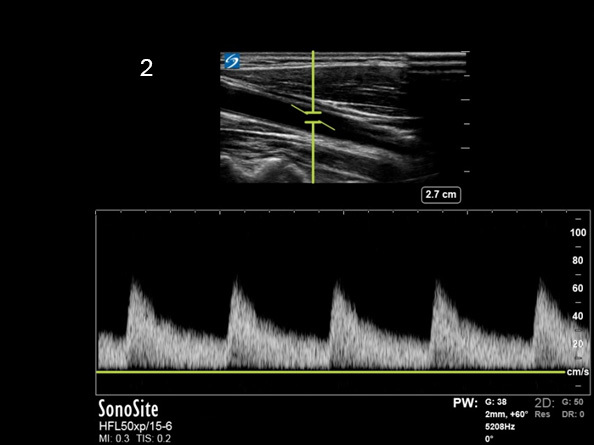

Instrumentation Scale Adjusted Image